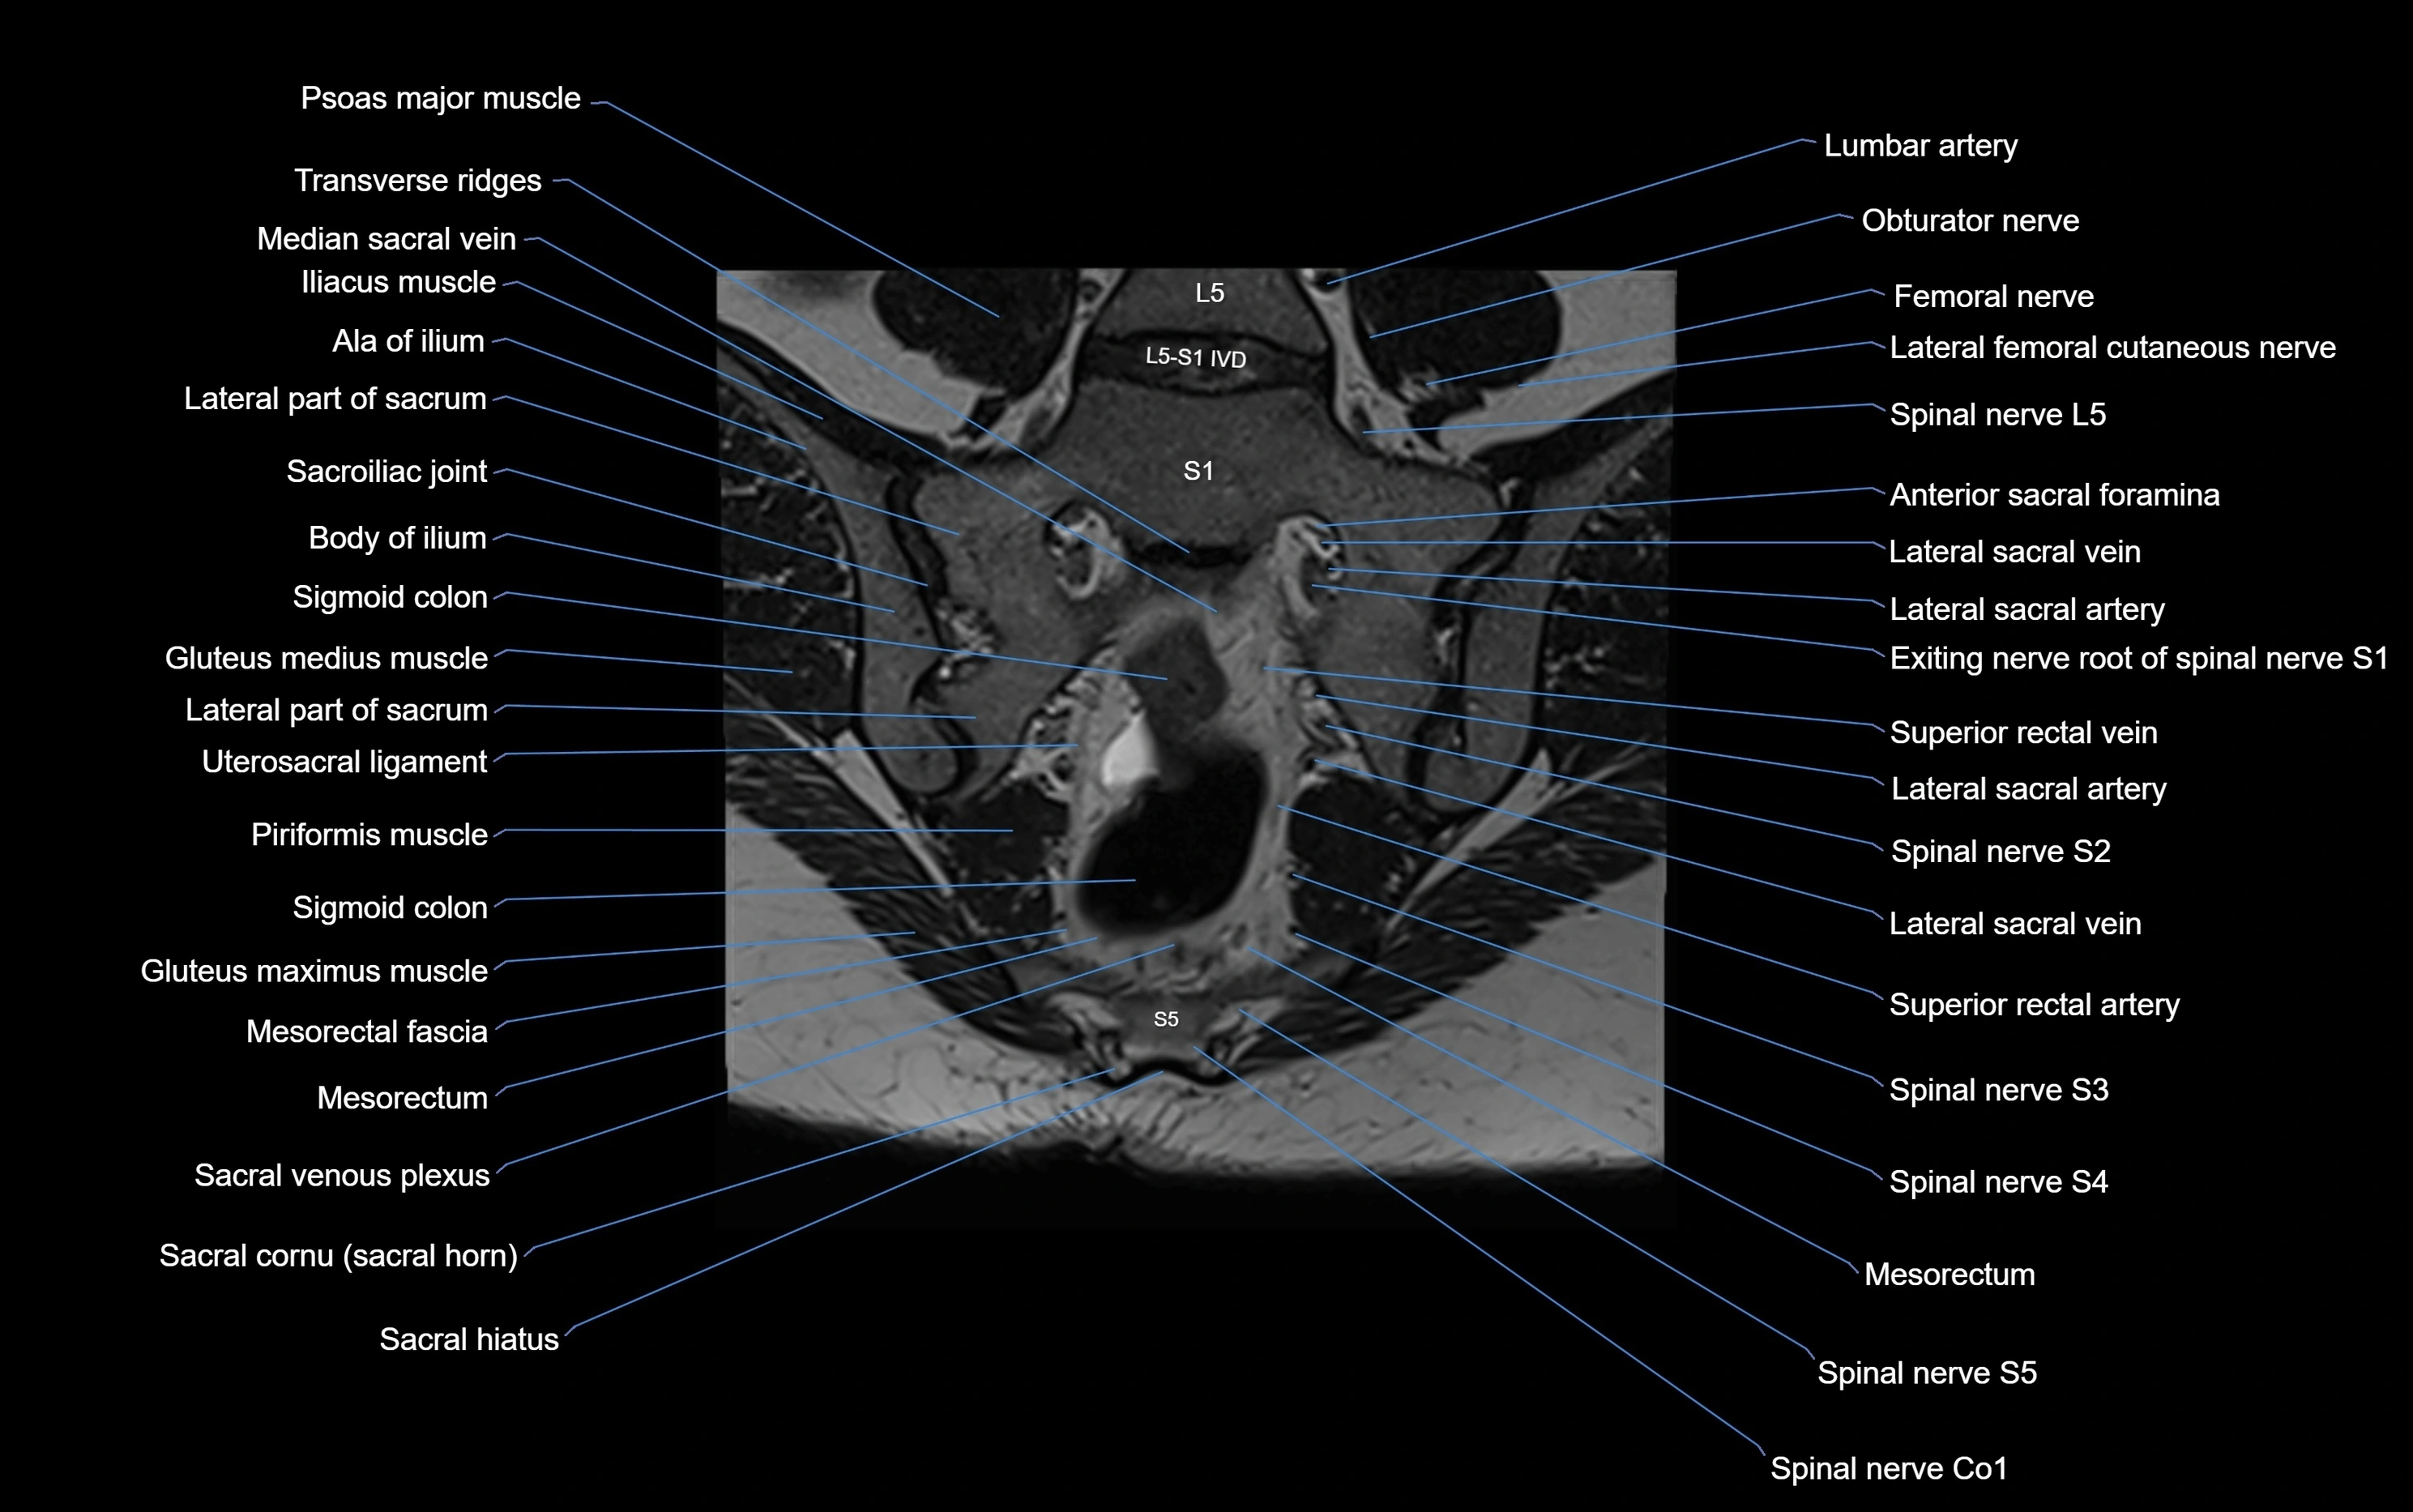

MRI Appearance

T1-weighted images:

• Cortical bone appears very low signal (dark); marrow shows intermediate signal

• Iliac fossa fat is bright against low-signal cortex

T2-weighted images:

• Cortical bone remains dark

• Marrow signal varies depending on fat content; edema or tumor shows hyperintensity

STIR:

• Suppresses fat, making bone marrow edema, fractures, or infiltrative lesions appear bright

• Excellent for trauma, sacroiliitis, and metastatic evaluation

T1 Fat-Saturated (Pre-contrast):

• Marrow: intermediate signal, fat suppressed

• Useful for detecting subtle marrow abnormalities adjacent to iliac cortex

T1 Fat-Saturated Post-Contrast (Gadolinium):

• Enhances vascularized structures, marrow pathology, tumors, and inflammatory changes

• Highlights soft tissue or bone invasion in pelvic neoplasms

MRI Non-Contrast 3D Imaging:

• Provides 3D morphology of iliac wing, crest, and articulations

• Used in preoperative planning for pelvic surgery and trauma reconstruction

MRI image

image